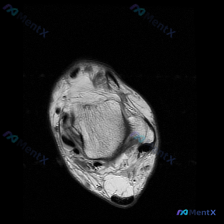

踝关节MRI见软组织积液,只看报告你会漏了这个关键病变吗?

最近看到这例踝关节MRI读片讨论,问题是「图像中能观察到什么软组织液相关改变」,整理一下完整分析思路,分享给大家。

这是踝关节MRI冠状位T2加权图像,核心发现如下:

- 骨结构改变:胫骨远端、距骨、跟骨显影清晰,距骨穹窿内侧关节面可见局灶性高信号改变,边界清晰,呈楔形凹陷状,周围伴骨髓水肿样高信号,提示距骨骨软骨损伤(OLT)

- 关节间隙改变:踝关节间隙内可见异常高信号,存在明确关节积液

- 软组织与韧带改变:内侧三角韧带走行连续无中断,周围软组织轻微水肿;外侧结构未见明显韧带撕裂损伤;踝关节周围软组织存在轻度弥漫性水肿,考虑为关节病变继发反应